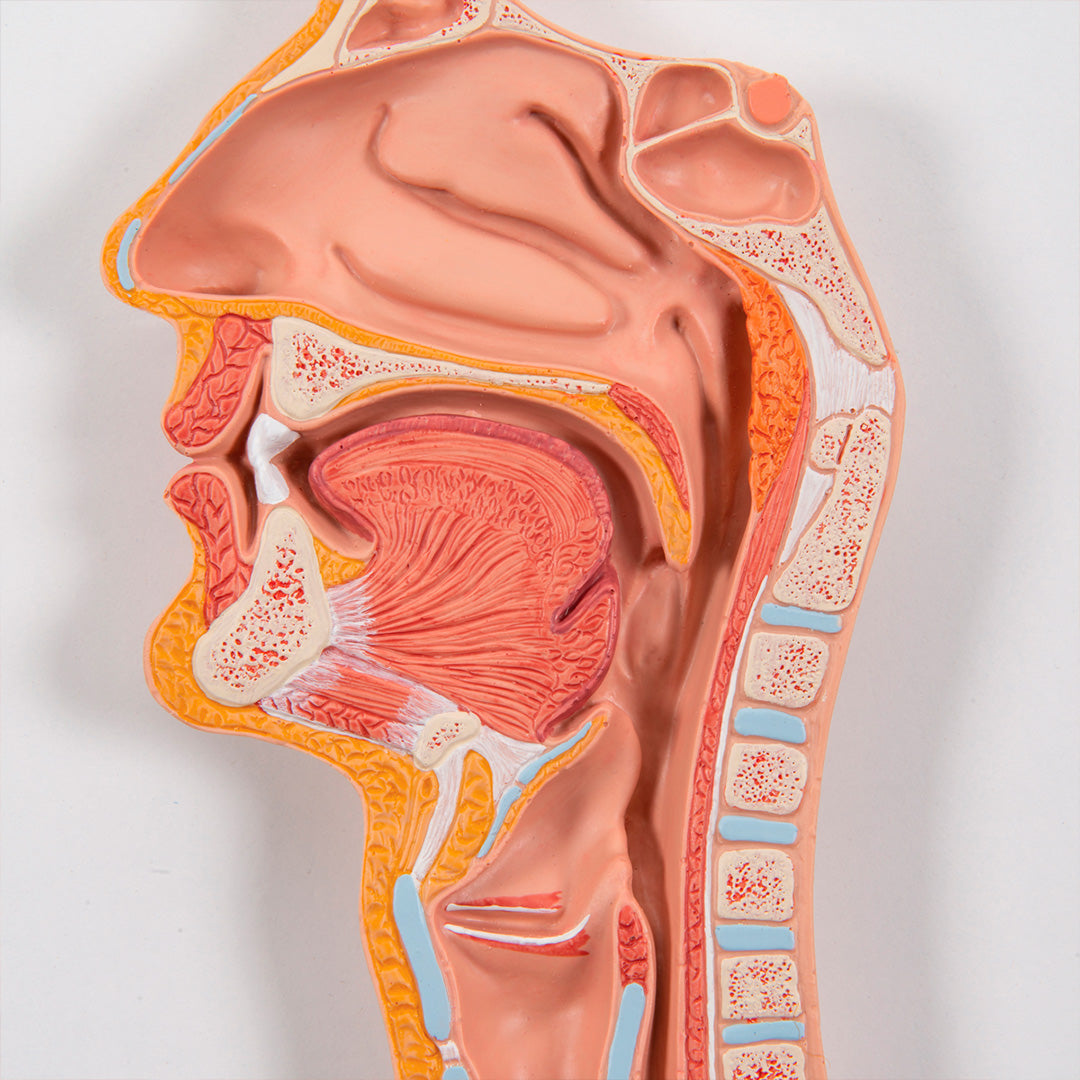

• Nariz

• Cavidad bucal y faringe

• Esófago